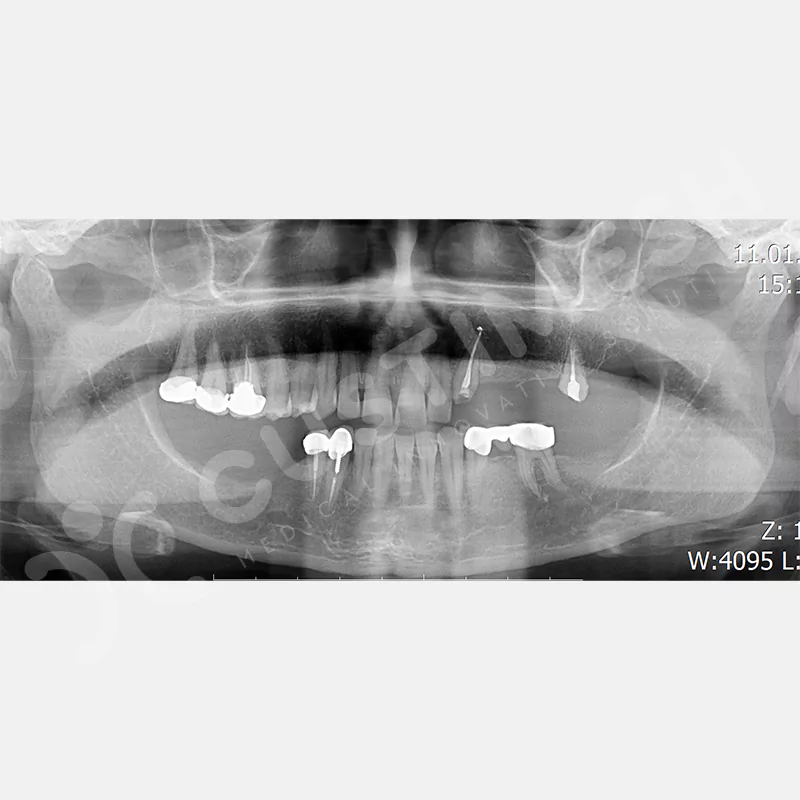

VAKA 2